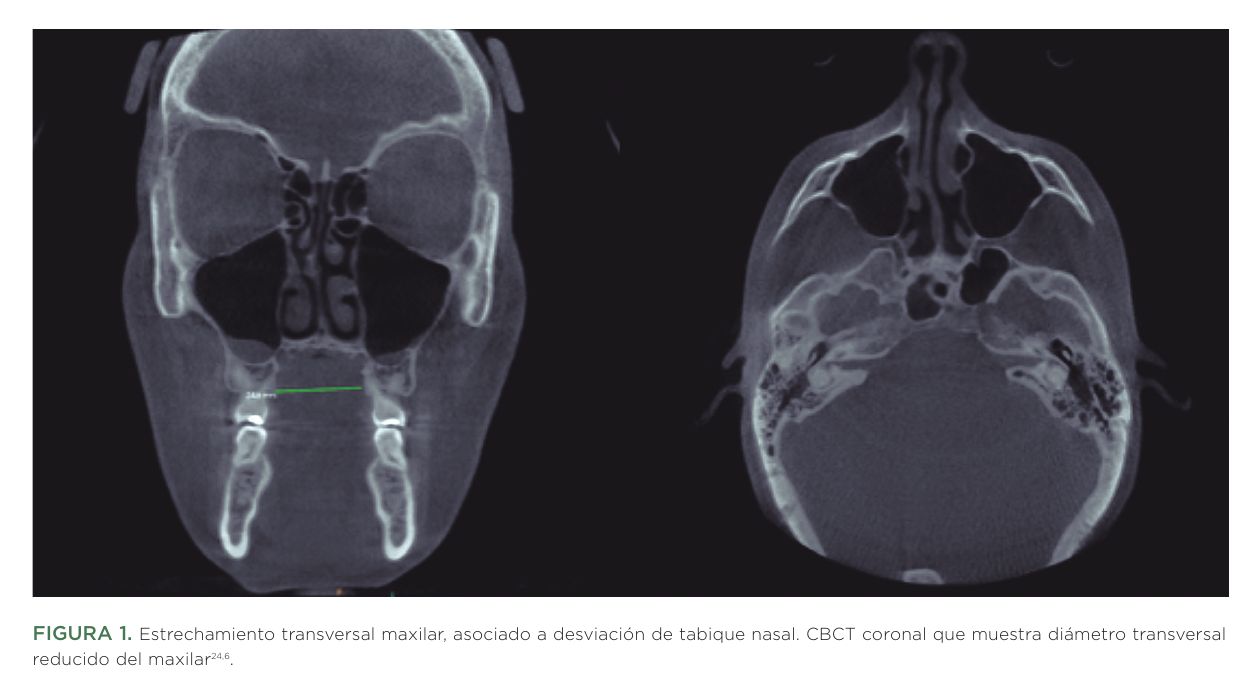

En las últimas décadas se ha intensificado el interés científico por comprender la relación entre la morfología maxilar y diversas dimensiones de la salud humana. La literatura emergente sugiere que un maxilar superior insuficientemente desarrollado puede asociarse con una vía aérea superior estrecha, alteraciones respiratorias durante el sueño, hipoxia intermitente, trastornos del crecimiento en etapas tempranas, disfunción cráneo-mandibular e incluso repercusiones sistémicas de carácter metabólico, inflamatorio o neurocognitivo y oncológico (Figura 1). Desde la estomatología, el análisis del maxilar superior trasciende la estética y función (oclusión): constituye una ventana clínica hacia la función respiratoria (somos seres aeróbicos, nuestras células necesitan O2 las 24 horas para obtener energía y que funcionen los órganos) la homeostasis postural, la calidad del sueño y el bienestar general del paciente. Por ello, investigar su relación con la salud humana no sólo es pertinente, sino necesario para un abordaje clínico más preventivo y multidisciplinar.

Estudios cefalométricos y tomográficos han mostrado correlaciones entre paladares altos/estrechos y disminución del volumen de la cavidad nasal, lo que se traduce en mayor resistencia inspiratoria9. Un maxilar estrecho reduce el volumen nasal interno, incrementa la resistencia inspiratoria y favorece la respiración bucal.